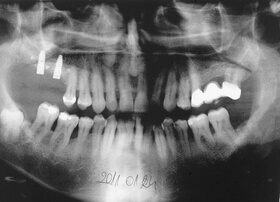

Több, mint tízéves hidak, elkopott fogak. Kezelési terv: a régi hidak cseréje és a többi fog ellátása fém-kerámia koronákkal

Az elkészült fém-kerámia koronák, hidak